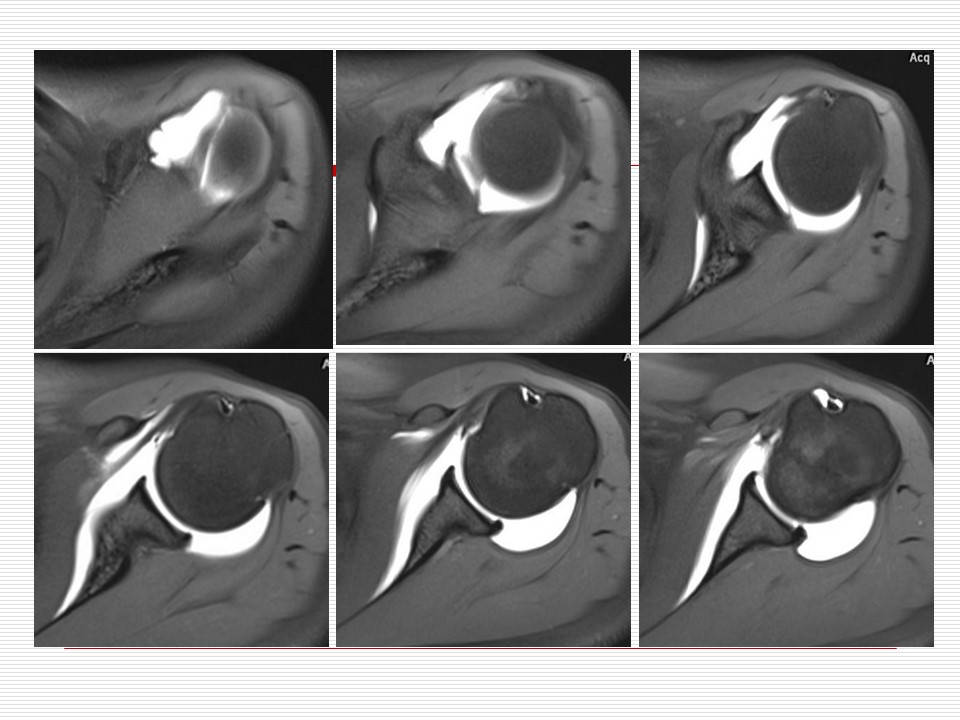

“肩关节解剖及其损伤的MR诊断PPT” 的相关文章